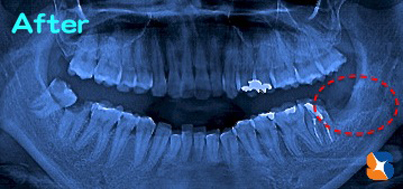

抜歯後のレントゲン 抜歯後

抜歯を開始したものの、アゴに鍵が掛けられている?かのように口が開かず、「さすがに今日こそ中止、断念か…」と頭をよぎりましたが、なんとか無事に抜歯が出来ました(よかった…ホッ)。 次の日、消毒に来られた患者様の口は通常に戻っておられました。